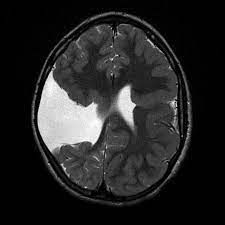

Schizencephaly refers to abnormal cleft in the brain. These clefts are lined by grey matter. It is a rare developmental disorder. The individual with schizencephaly may be diagnosed antenatally, whereas in adult life, it may present with motor disturbances and seizures. Reference: https://radiopaedia.org/articles/schizencephaly Image via: https://radiopaedia.org/articles/schizencephaly